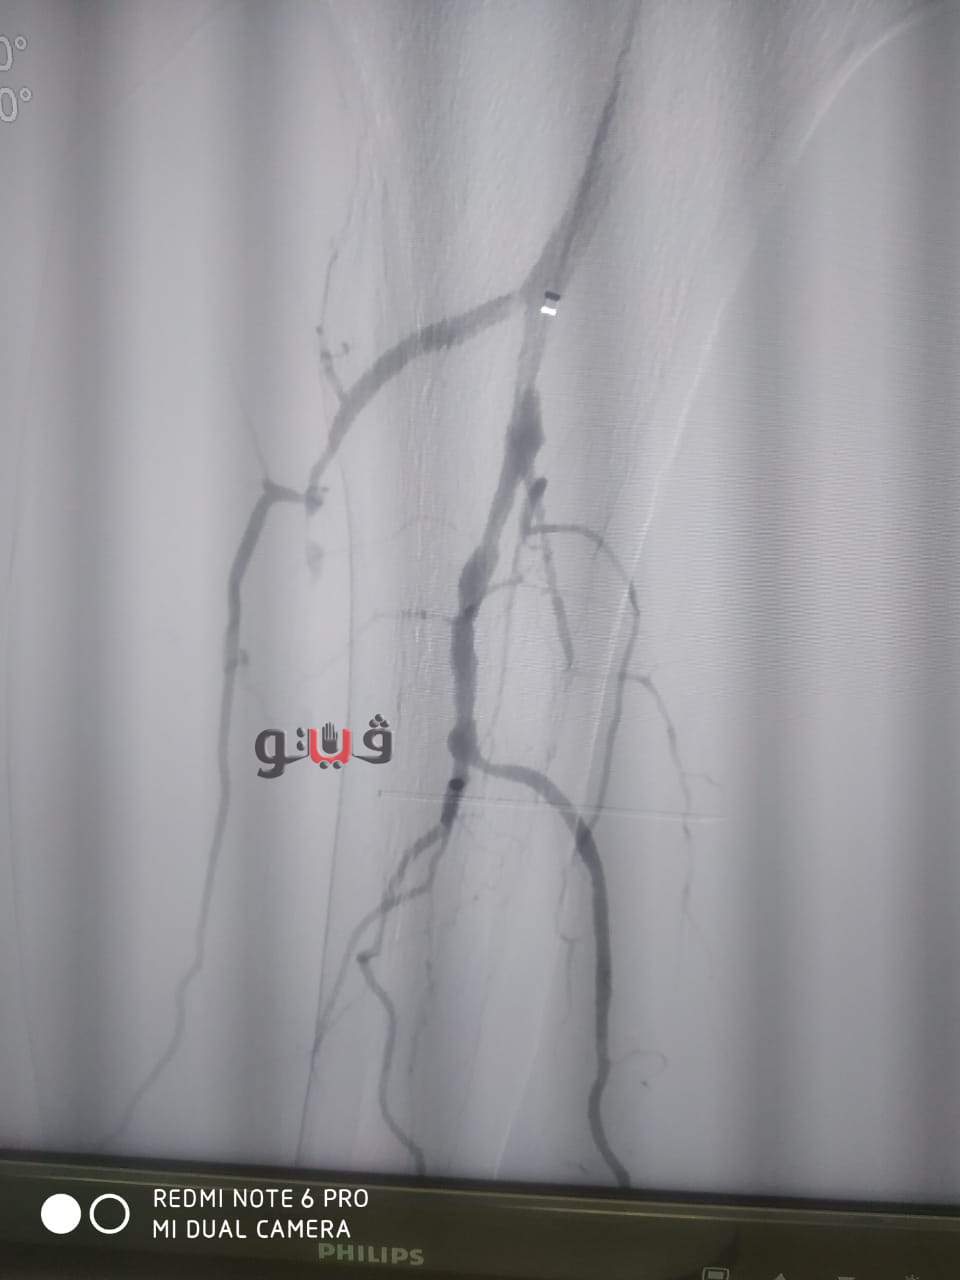

نجاح عملية توسيع بالوني بالقسطرة الطرفية لمريض بمستشفى المنصورة الدولي

شهد مستشفي المنصورة الدولي بمخافظة الدقهلية نجاح فريق طبي بإجراء عملية توسيع بالوني لمريض يبلغ من العمر 65عاما يعاني من قصور دموي حرج بالساق اليمنى.

وأوضح مكي انه تم التدخل الطبي السريع عن طريق القسطرة الطرفية داخل وحدة القسطرة التداخلية بمستشفى المنصورة العام الجديد (الدولي) وتم استعادة وتقوية الدورة الدموية للساق بنجاح عن طريق فريق طبي من قسم جراحة الاوعية الدموية بالمستشفى حيث تمت العملية بنجاح باهر وخرج المريض من العمليات بحالة مستقرة.